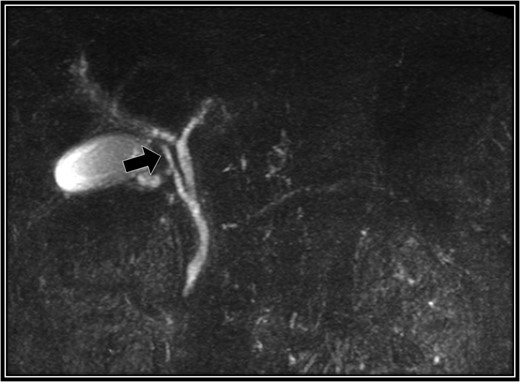

A 48-year-old Japanese man experienced abdominal pain after dinner. He underwent computed tomography (CT), and we observed stones in his cystic duct (Fig. 1). Hematological findings showed no liver dysfunction. A magnetic resonance cholangiopancreatography (MRCP) scan demonstrated that the right accessory hepatic duct branching from the cystic duct dominated an anterior segment of the right hepatic lobe (Fig. 2). Therefore, we diagnosed him as cholelithiasis with an anomalous biliary tract, and LC was planned.

Preoperative magnetic resonance cholangiopancreatography scan. The right accessory hepatic duct branching from the cystic duct (black arrow) dominates an anterior segment of the right hepatic lobe.